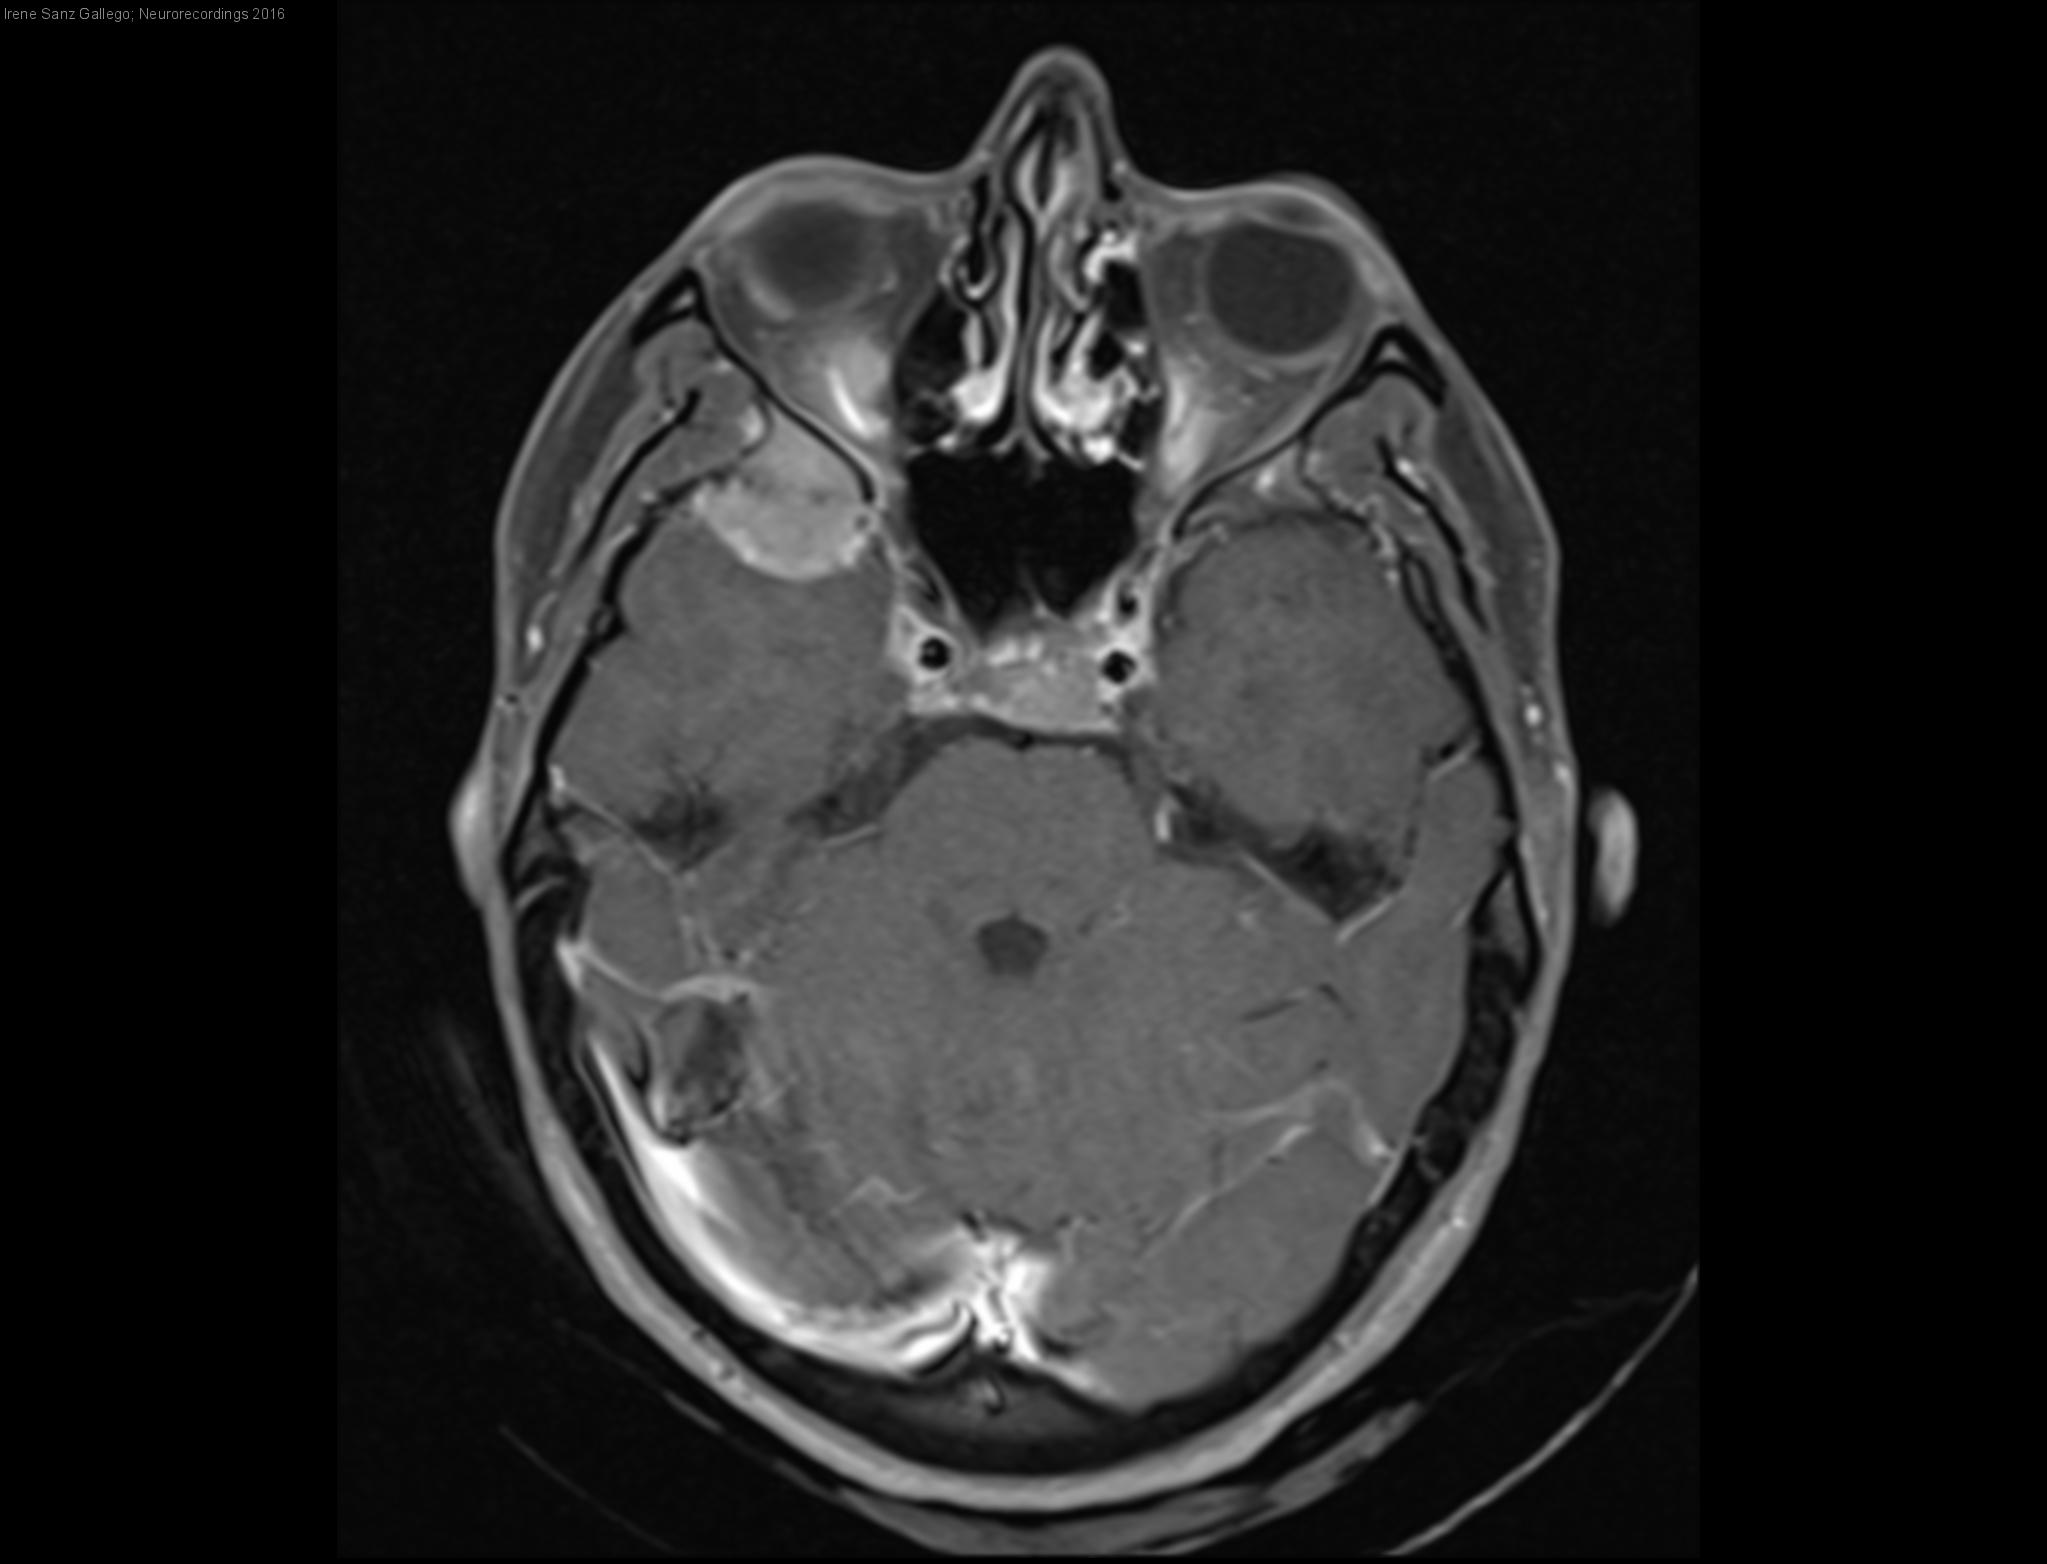

Parálisis de III y IV nervios craneales izquierdos secundaria a metástasis cerebrales

Mujer | 31 años

Diagnóstico final: Carcinoma gástrico estadío IV

Mujer de 31 años, fumadora, que consultó en Urgencias por cefalea frontal izquierda de cuatro días de evolución, opresiva, continua y con aumento de intensidad progresivo. Asociaba sonofobia, fotofobia y vómitos, no interfería con el descanso...